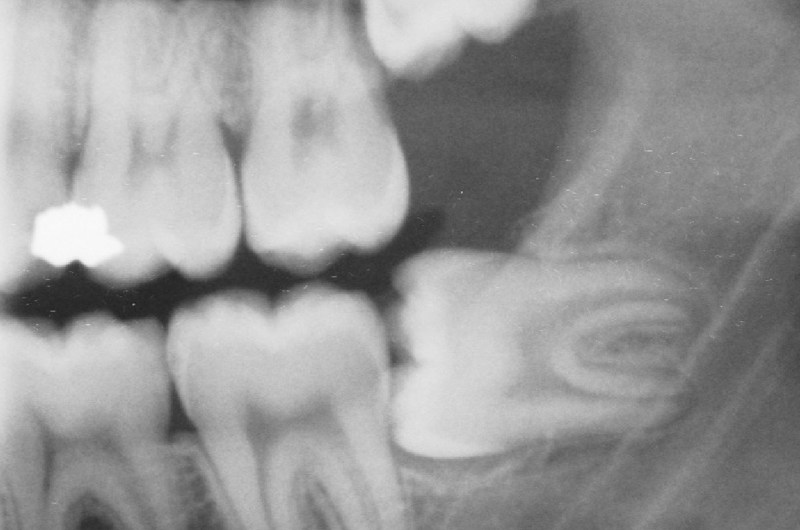

På røntgenbilledet er visdomstanden kommet normalt frem i munden.